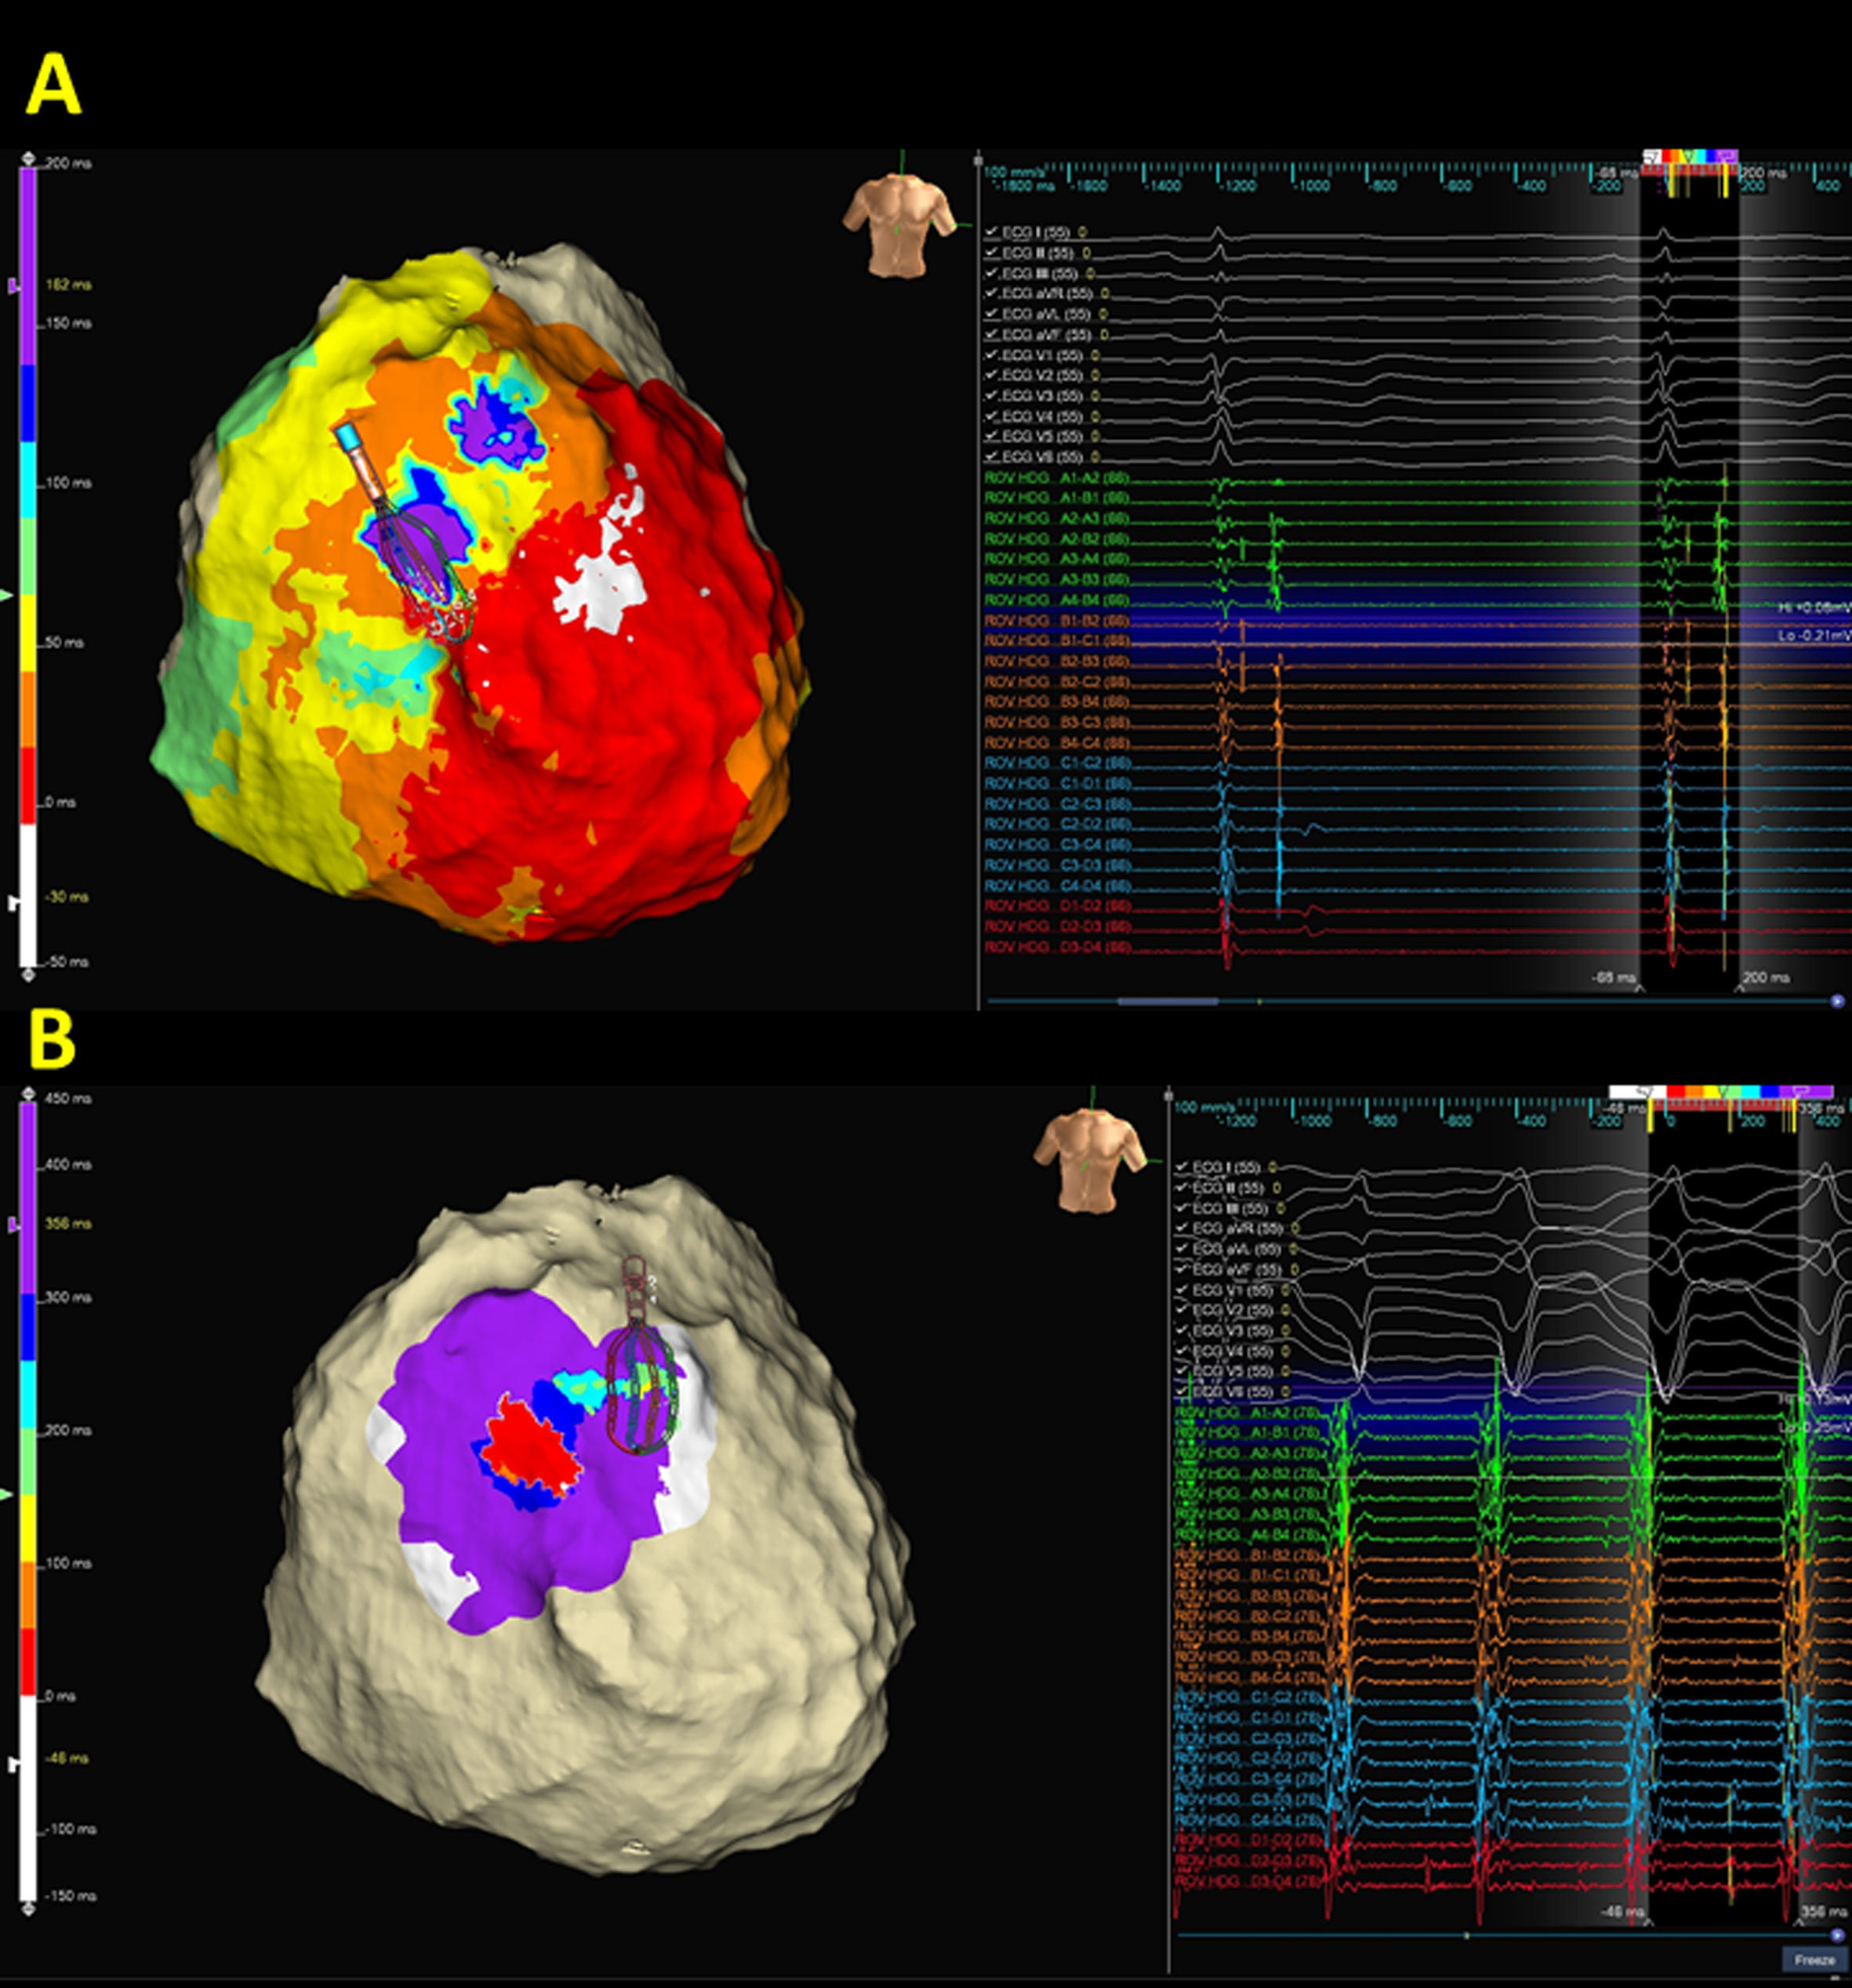

Although VF/ventricular flutter is not uncommon, macroreentrant VTs remain the most common manifestation of ventricular tachyarrhythmias in ARVC [76]. Ideally, delineation of VT circuits and targeting the critical isthmuses of VTs to terminate VTs, especially mappable VTs, would be the perfect strategy for VT ablation in ARVC. However, due to the three-dimensional VT circuits in ARVC, an incomplete epicardial circuit with an activation gap with endocardial focal centrifugal activation pattern might be encountered (Figs. 3,4). Entrainment from the earliest activation sites and the adjacent scar might provide information on the potential exit or surrogates of the reentrant circuits (Fig. 3) [77].

Fig. 4.

Fig. 4.A representative case demonstrates the correlation between deceleration zone and ventricular tachycardia (VT) isthmus. (A) isochronal late activation map (ILAM) of epicardial substrates. Compared to the bipolar voltage map (Fig. 2), ILAM provided informative and functional properties of the two deceleration zones within the RV outflow epicardium. (B) VT activation demonstrated that the VT circuit is compatible with the superior isochronal crowding region. Notably, an incomplete epicardial circuit with an activation gap is recorded, and both far-field and near-field potentials are recorded by high-density mapping.

Regardless of the mechanistic insights provided by the activation map of VT, substrate modifications, either through elimination of local abnormal ventricular activity [25] isolated delayed component ablation [42] core isolation [78], or scar dechanneling [79], have been used to facilitate non-inducibility of VT with promising results. Although extensive substrate modification might provide a better outcome [13], it could be time-consuming and may carry a higher risk of complications. In addition, it has been proven that not all abnormal substrates are actively involved in the VT isthmus [37]. Therefore, various ablation strategies have been proposed to target the abnormal substrates responsible for the VT isthmus without sacrificing clinical efficacy, such as decrement evoked potential mapping [67], hidden slow conduction electrograms [68], omnipolar mappings [80], and strategic multielectrode positioning for VT mapping (Fig. 4) [44].